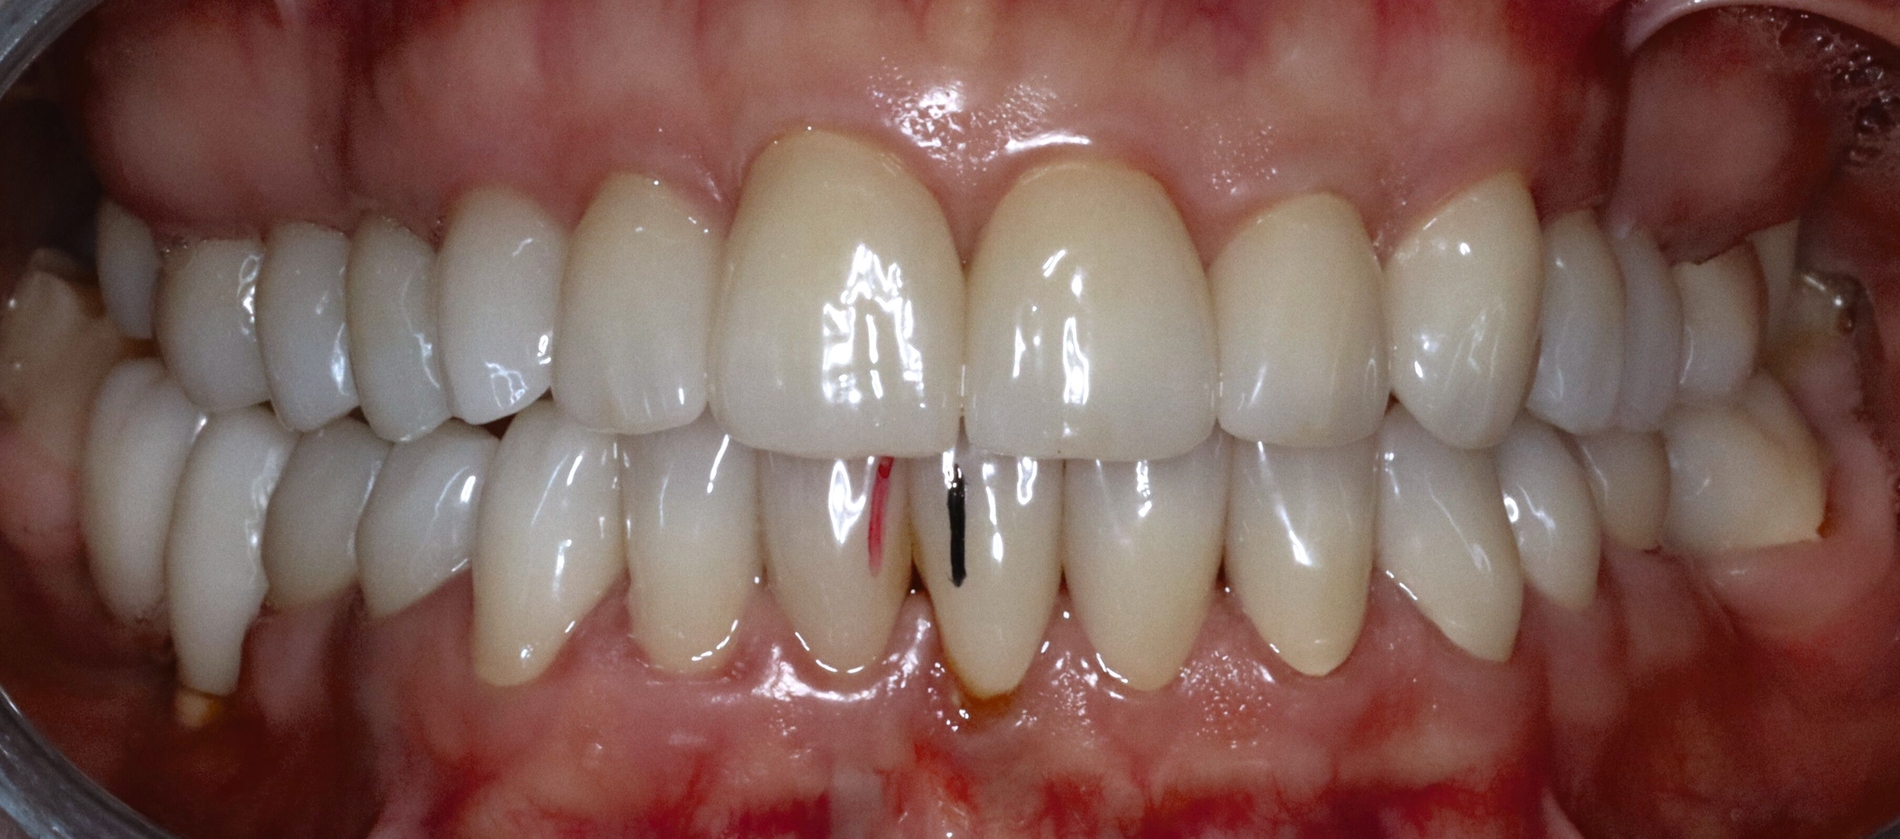

Die Patientin schilderte eine deutliche Instabilität des Zusammenbisses mit punktuellem Kontakt auf der linken und fehlenden Zahnkontakten auf der rechten Seite seit dem Tag der Insertion des Zahnersatzes. Ein annähernd stabiler Zahnkontakt sei nur durch aktiven Verschub des Unterkiefers nach rechts im Sinne eines Eingleitens in die Interkuspidation des Zahnersatzes erreichbar. Bei Provokation dieser „schiefen“ Unterkieferposition komme es jedoch aufgrund der muskulären Anstrengung nach kurzer Zeit zu Beschwerden. Die Patientin gab in diesem Zusammenhang Schmerzen und eine Grundanspannung der Kau-/Nackenmuskulatur und Kopfschmerzen an, jeweils links > rechts (Abbildung 4).

Die Sprechfunktion und die Funktion der mimischen Muskulatur (zum Beispiel Küssen) beschrieb sie als anstrengend und ermüdend. Die Kieferöffnung verlaufe schräg nach links und sei schmerzhaft eingeschränkt. Aufgrund der instabilen Zahnkontakte sei die Kaufunktion deutlich limitiert und beschwerlich. Im Bereich der linken Vorkontakte komme es wiederholt zu Einbissverletzungen und mechanischen Irritationen der Wangeninnenseite. Ebenso wurden Schmerzen im Zungenbereich links und zeitweise Empfindungen von Taubheitsgefühl beschrieben. Als ein weiteres Problem nannte die Patientin, dass der linksseitige Vorkontakt der Kronen dauerhaft bestehe und ein Nichtkontakt im Sinne einer Ruhelage nur durch kontinuierliche aktive Kieferöffnung möglich sei.

Mobilität des Unterkiefers eingeschränkt: Kieferöffnung aktiv ohne Schmerz 20 mm, aktiv mit myogenem Schmerz 32 mm, passiv 42 mm (Deflexion nach links, myogener Schmerz); unterdurchschnittliche Rechtslaterotrusion 4 mm und Linkslaterotrusion 6 mm (jeweils myogen schmerzhaft); Protrusion 4 mm (myogen schmerzhaft); Vertikaldimension unphysiologisch zu hoch (circa 2–3 mm) (Abbildungen 5 und 6).

Statische Vorkontakte 25/34 und 26/35 in geführter zentrischer Kondylenposition (entspricht dem subjektiven Erstkontakt) (Abbildungen 7 und 8) mit forcierbarem Gleiten in die maximale (Kronen)Interkuspidation circa 3 mm nach rechts (Abbildung 9).